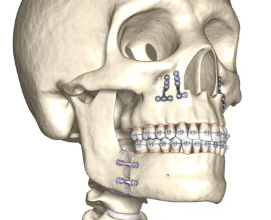

양악수술은 턱의 균형을 맞추고 기능적, 심미적인 문제를 해결하기 위해 이루어지는 복합적인 수술입니다. 수술 후에는 일정한 회복기간과 관리가 필요하며, 개인에 따라 차이가 있기는 하지만 일반적으로 몇 가지 공통적인 단계로 나누어집니다. 이 글에서는 양악수술 회복기간과 각 단계에서의 특징, 관리 방법을 폭넓게 알아보겠습니다.

양악수술 후 완전한 회복까지는 약 6개월에서 1년의 시간이 걸릴 수 있습니다. 이 시기에는 세부적인 변화를 경험하며, 꾸준한 관리가 필요합니다.

- 정기적인 병원 방문: 회복 과정을 지속적으로 점검받아야 하며, 필요시 교정이나 추가적인 치료를 받을 수 있습니다.

- 잔여 붓기 감소: 미세한 붓기가 자연스럽게 사라지며, 최종적인 얼굴 형태가 안정됩니다.

- 턱 기능 회복: 턱 관절과 근육의 사용이 점차 자연스러워지고, 수술 전과 같은 기능을 회복합니다.